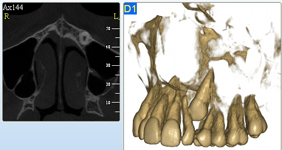

NewTom Giano

Jedná se o nejnovějším přístroj ze skupiny dentálních hybridních CBCT (3D) + 2D (pan i ceph) systémů. Opět umožňuje na základě jediného snímkování vytvořit všechny typy RTG zobrazení, které jsou pro lékaře potřebné. Používaná technologii tzv. „kuželového paprsku“ a speciální senzory pro minimální zátěž při snímkování pacienta.

Vyšetření pomocí tohoto přístroje (nebo

3D DVT - NewTom) a získaná data používáme

pro každou implantaci, dále ve stomatochirurgii (zlomeniny čelistí, zuby moudrosti, cysty, onemocnění čelistního kloubu), ortodoncii (retinované zuby, nadpočetné zuby), parodontologii atd.